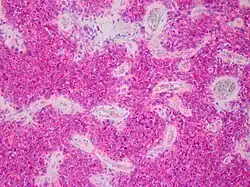

| Micrograph of an H&E stained section of a peripheral PNET. | |

It is classified into two types, based on location in the body: peripheral PNET and CNS PNET.

Peripheral PNET

The peripheral PNET (pPNET) is now thought to be virtually identical to Ewing sarcoma:

"Current evidence indicates that both Ewing's sarcoma and PNET have a similar neural phenotype and, because they share an identical chromosome translocation, they should be viewed as the same tumor, differing only in their degree of neural differentiation. Tumors that demonstrate neural differentiation by light microscopy, immunohistochemistry, or electron microscopy have been traditionally labeled PNETs, and those that are undifferentiated by these analyses have been diagnosed as Ewing's sarcoma."[5]